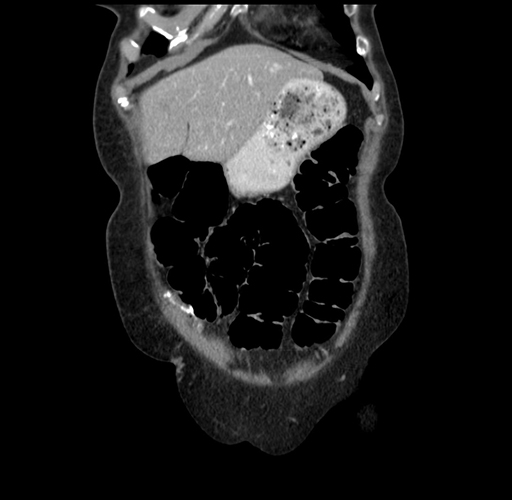

Pre-Chemo: Coronal Venous

Coronal Venous